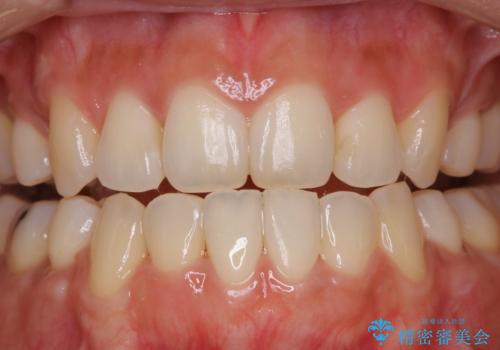

- 約1年前に矯正治療が終了し、その後のメンテナンスを行っている方です。矯正のチェックもかねてクリーニングも希望とのことでした。

PMTC(自費クリーニング)30分コースを行いました。

定期的なメンテナンスをして頂いていること、ご自身でのケアをかなり丁寧にされていていることで、歯石や着色の量がさほど多くなかったため30コースで全体的なクリーニングが可能でした。